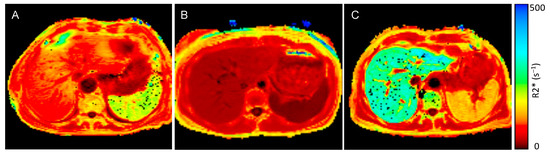

Figure 2.

MRI R2* map of a patient with anemia and end-stage kidney disease (ESKD), control individual, and a patient with transfusion-related iron overload: (A) R2* maps of an anemic ESKD patient (spleen R2* value 189.7 s−1, liver R2* value 88.4 s−1), (B) R2* map of an otherwise healthy control individual without inflammation (spleen R2* value 15.3 s−1, liver R2* value 29.1 s−1) and (C) a patient with transfusion-related iron overload (spleen R2* value 126.0 s−1, liver R2* value 290.3 s−1)—dark red represents low R2* values and low iron concentrations, bright red and orange represents higher R2* values and higher iron concentrations, yellow and green represent the highest iron concentrations.